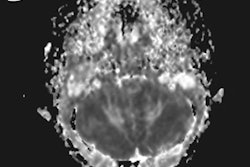

Alzeca is developing its ADx nanoparticle technology to enable MRI scanning of Alzheimer's disease as an alternative to PET. ADx can carry an encapsulated imaging agent across the blood-brain barrier and bind to amyloid plaque, allowing patients to be imaged with a standard clinical MRI scanner.